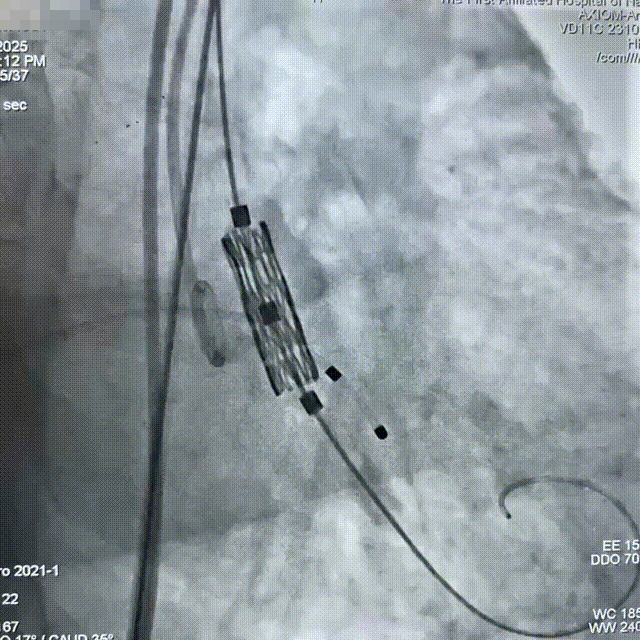

交换为预塑性的加硬钢丝至左心室,然后送入预装有Myval™ 20mm瓣膜的输送系统,成功完成跨瓣操作到达主动脉根部,调整瓣膜深度;

参考术前CT测量值,调整瓣膜至释放前最佳高度,缓慢释放近1/3长度时复查主动脉根部造影,确认瓣膜高度适合,临时起搏180次/分,以80:20比例13mL快速释放瓣膜至瓣膜工作区完全打开,于标准位置释放瓣膜;